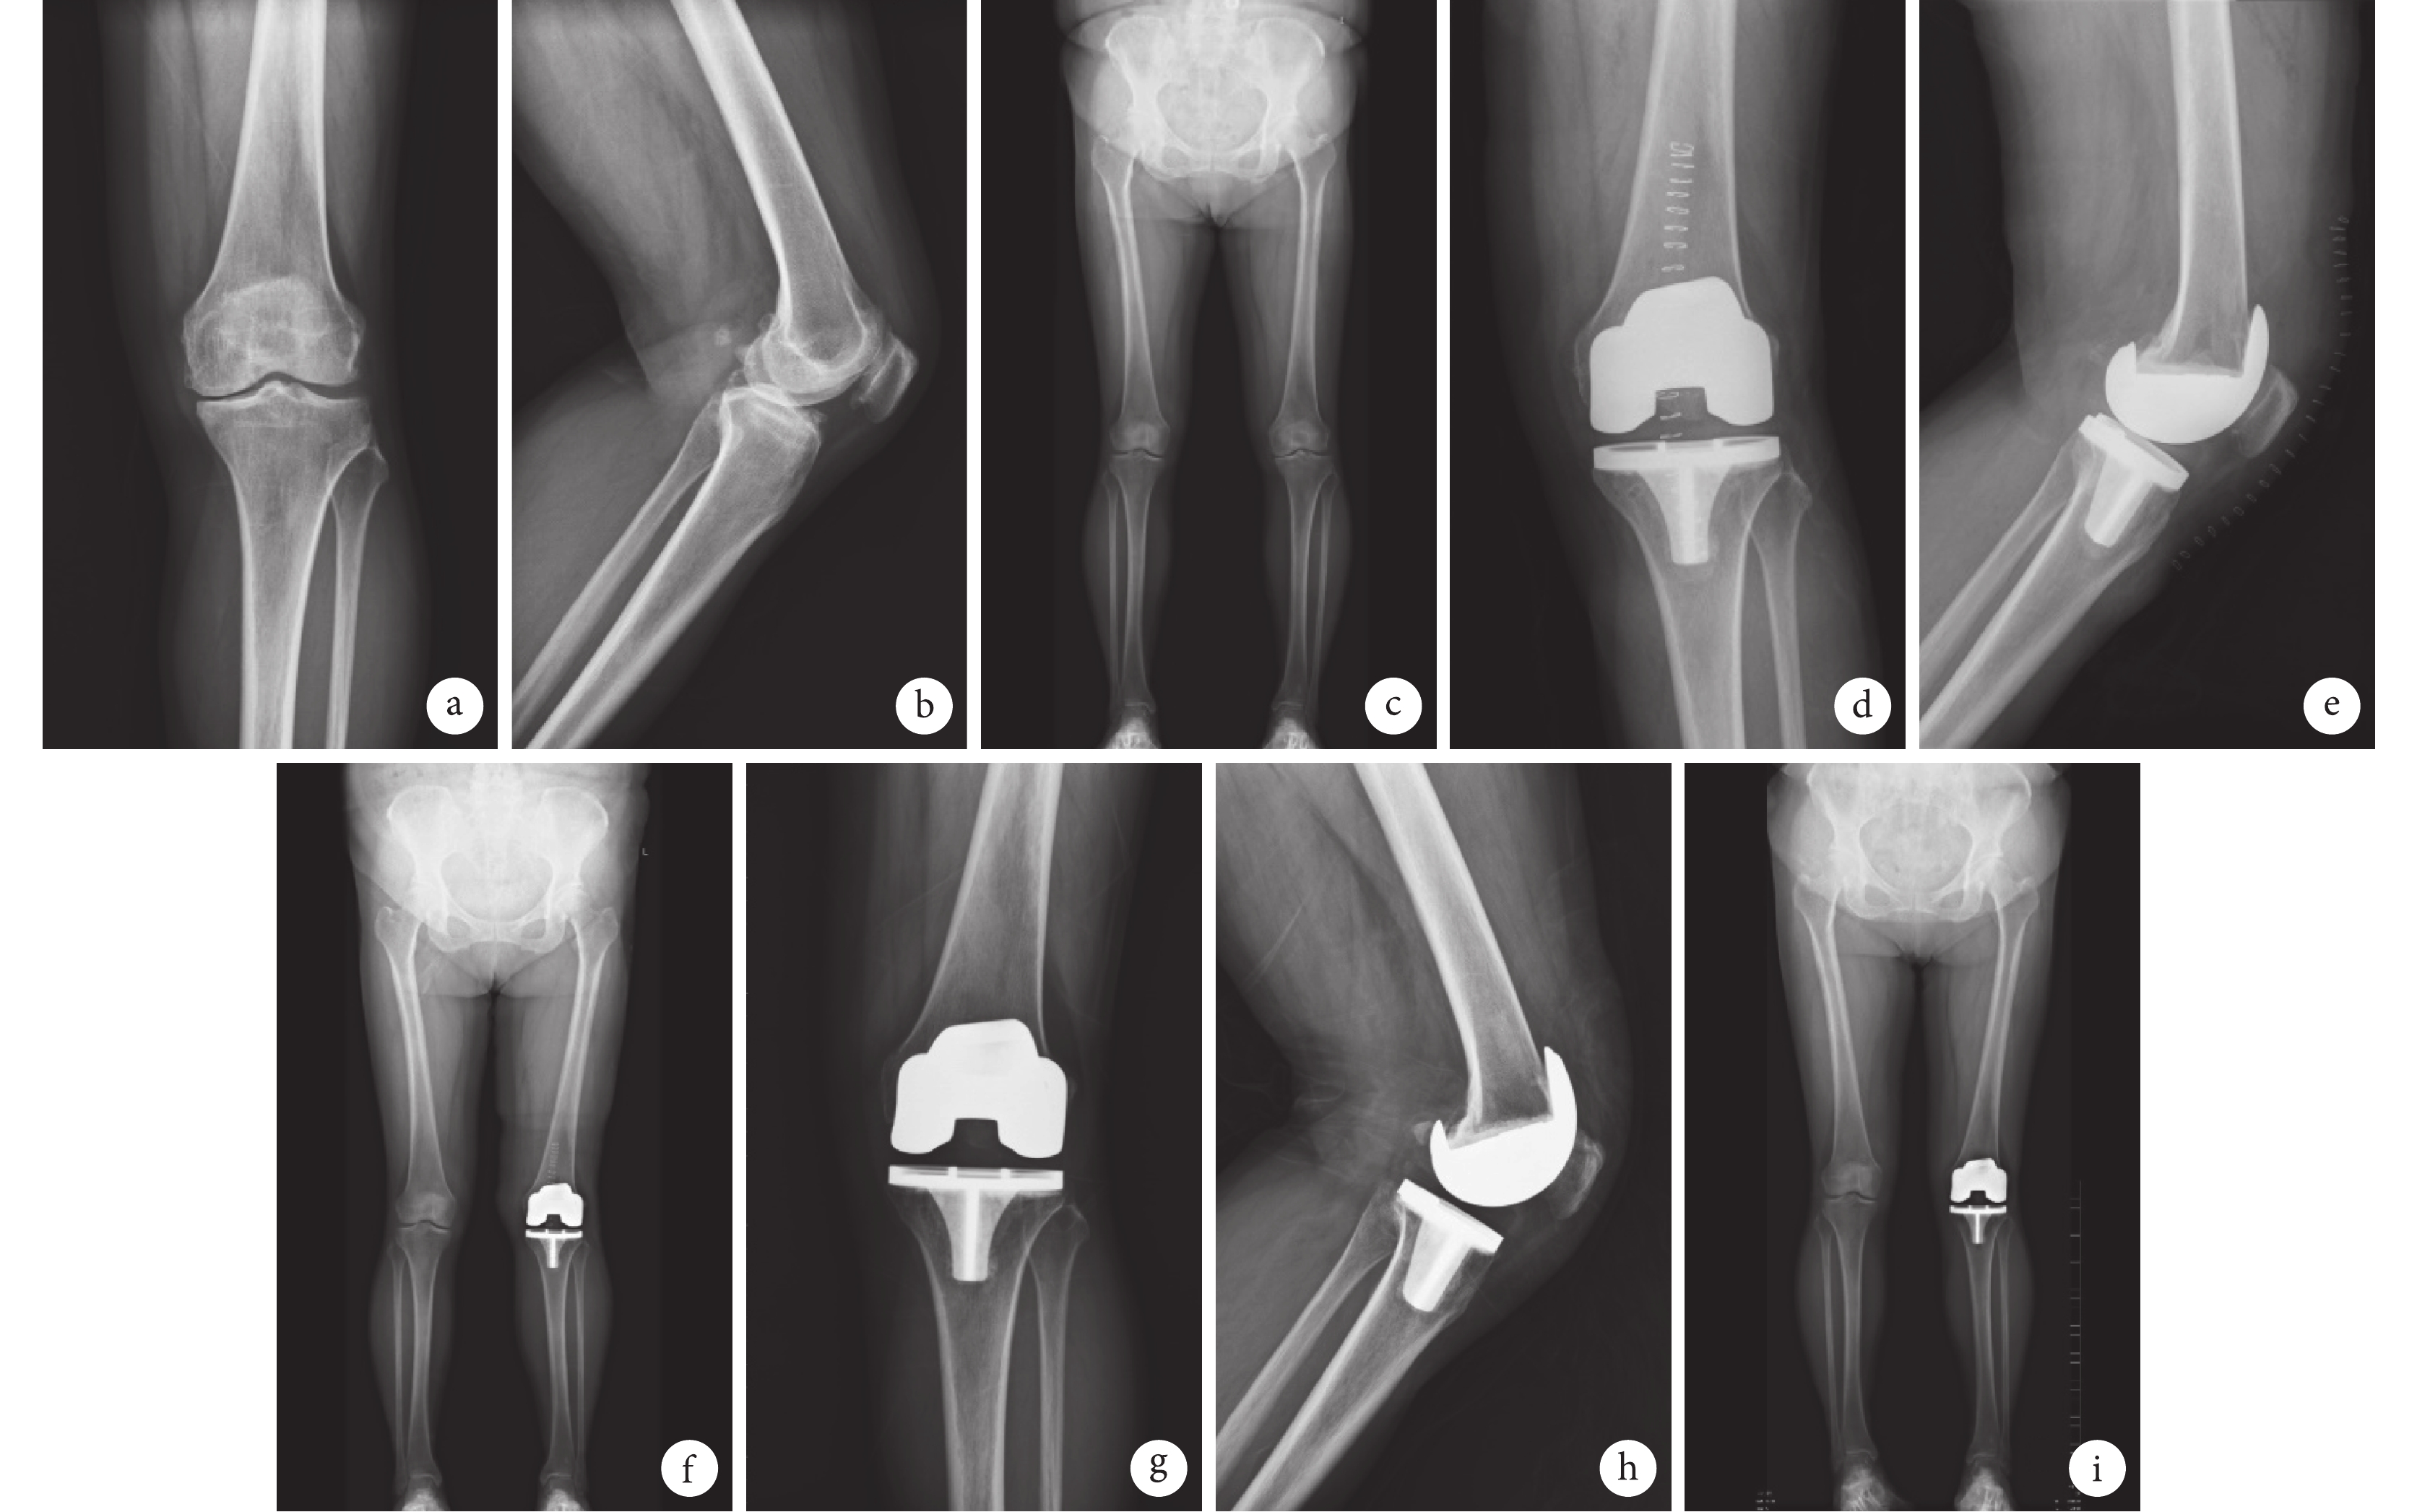

X 線片復查示兩組患者下肢力線恢復良好,隨訪期間假體周圍均未見透亮線,無假體松動及墊片脫位發生,無翻修患者,Kaplan-Merier 法評估假體生存率為 100%。術后 1 周測量兩組 FTA、HKA 均較術前改善,差異有統計學意義(P<0.05)。見表 3及圖 1、2。

a~c. 術前;d~f. 術后 1 周示假體位置及下肢力線良好;g~i. 術后 32 個月示假體位置滿意、無松動,下肢力線良好

Figure1. A 50-year-old male patient with severe medial compartment OA of right knee in the UKA group, and X-ray films of anteroposterior view, lateral view, and full length view of both lower limbs, respectivelya-c. Before operation; d-f. At 1 week after operation, the position of prosthesis and the alignment were good; g-i. At 32 months after operation, the position of prosthesis was satisfactory without loosening, and the alignment was good